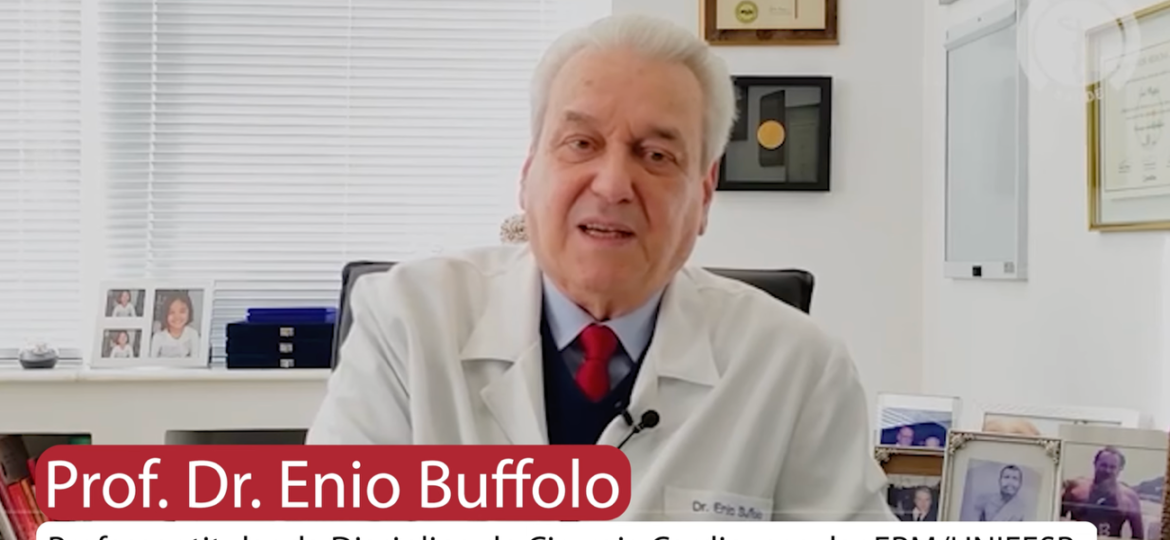

Nascido em 9 de dezembro de 1941, em São Paulo, Enio Buffolo escolheu seguir carreira na medicina após realizar um…

Dr. Paulo Roberto B. Evora: “Todo cirurgião deve ser um cientista” Prof. Paulo Evora é formado em Medicina na Faculdade…